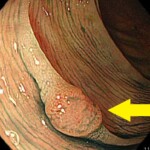

①のポリープはこんな感じです。簡単に切除できます。